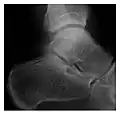

The greater tuberosity of the humerus is also an illustrative location of occult fractures. The osseous injury may follow seizures, glenohumeral dislocation, forced abduction, or direct impaction. They are commonly discovered on MRI in symptomatic patients with suspicion of rotator cuff tear. Coronal images are best suited for detection. They appear as crescentic oblique lines surrounded by a bone marrow edema pattern (Figure 5). The rotator cuff must be inspected since associated ligamentous lesions are common. In the ankle, malleoli and tarsal bones should be checked carefully for any cortical disruptions and radiolucent lines that may reveal a fracture. Awareness of the exact location of the pain will help direct the attention of the interpreter when searching for very subtle signs of fracture (Figure 6).[1]

-

a -

b

Figure 6: Subtle anterior talar fracture in a 39-year-old man presenting with ankle pain after a fall. (a) Anteroposterior radiograph shows a subtle oblique radiolucent line through the talus (white arrows). (b) Sagittal CT reformation confirms the presence of an anterior talar fracture with cortical offset (black arrow). Avulsion fractures, which consist of a detached bone fragment resulting from a ligament or tendon pulling away from the bone, may also present with subtle radiographic signs. Tiny osseous fragments near the presumed attachment site of a ligament suggest this diagnosis. Common sites are the lateral tibial plateau (the Segond fracture), the spinal tuberosity of the tibia resulting from anterior cruciate ligament avulsion, and the ischial tuberosity.[1]